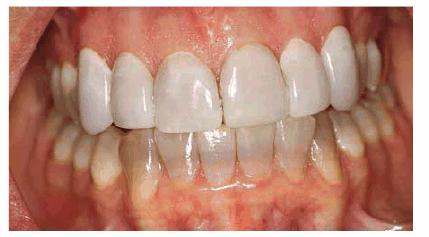

either on an individual tooth or on all teeth (Figures 16-1A, and 16-1B). There are many causes and

Figure 16-1A: An otherwise attractive smile is marred by discolored teeth.

Figure 16-1B: After tooth lightening, the smile is much more pleasing.